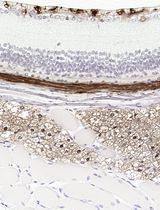

Improved Immunohistochemistry of Mouse Eye Sections Using Davidson's Fixative and Melanin Bleaching

Anne Nathalie Longakit [...] Catherine D. Van Raamsdonk

Nov 20, 2025 1628 Views